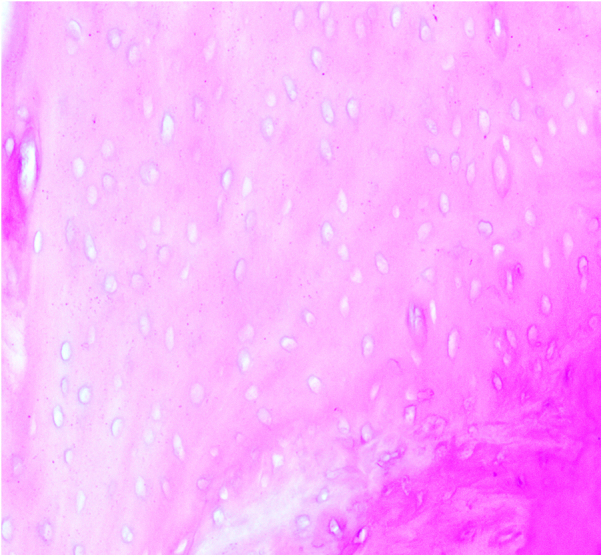

本研究旨在探讨自然杀伤细胞(NK)在股骨头骨坏死(ONFH)中RANKL/RANK/OPG通路中的作用。将C57小鼠分为对照组、观察组(每组10只)和实验组(4只NK细胞敲除小鼠)。采用脂多糖联合甲基强的松龙给药8周,建立激素性股骨头坏死模型。观察组患者皮下注射等量生理盐水。8周后取小鼠外周血,死后取双侧股骨头标本。采用PCR和ELISA技术检测ONFH小鼠外周血和关节液中NK细胞、OPG、RANK、RANKL的表达水平,并与对照组进行比较。与对照组相比,实验组外周血和关节液中NK细胞数量增加。OPG表达下调,RANK和RANKL显著上调,导致成熟破骨细胞数量明显增加。在ONFH患者中,NK细胞上调TNF-α和RANKL,下调IFN-γ和OPG,促进破骨细胞成熟,破坏骨平衡,加速股骨头坏死塌陷,最终加速股骨头坏死的进展。

This study aimed to investigate the role of natural killer (NK) cells in the RANKL/RANK/OPG pathway in osteonecrosis of the femoral head (ONFH). C57 mice were categorized into a control group, an observation group (10 mice each), and an experimental group comprising 4 NK cell knockout mice. A hormone-induced femoral head necrosis model was created by administering lipopolysaccharide combined with methylprednisolone for 8 weeks to the experimental and control groups. The observation group received subcutaneous injections of an equal amount of normal saline. After 8 weeks, peripheral blood was collected from the mice, and bilateral femoral head specimens were obtained post-mortem. Expression levels of NK cells, OPG, RANK, and RANKL in the peripheral blood and joint fluid of ONFH mice were determined using PCR and ELISA techniques, and compared with the control group. The experimental group exhibited an increased number of NK cells in the peripheral blood and joint fluid compared to the control group. OPG expression was downregulated, while RANK and RANKL were significantly upregulated, resulting in a marked increase in the number of mature osteoclasts. In ONFH patients, NK cells were found to upregulate TNF-α and RANKL, downregulate IFN-γ and OPG, promote osteoclast maturation, disrupt bone balance, accelerate femoral head necrosis collapse, and ultimately hasten the progression of femoral head necrosis.